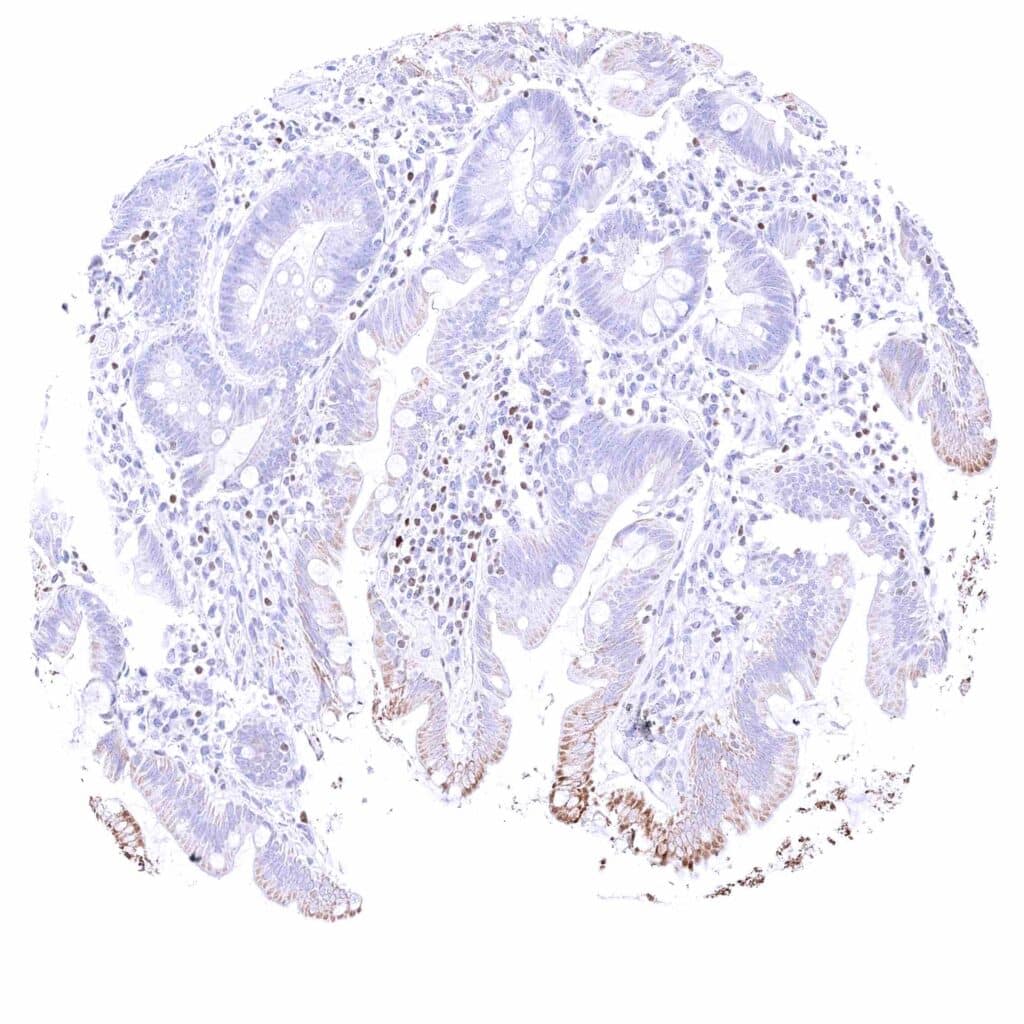

Rectum, mucosa – Nuclear GATA3 positivity of some lymphocytes. Granular cytoplasmic GATA3 staining of epithelial cells.